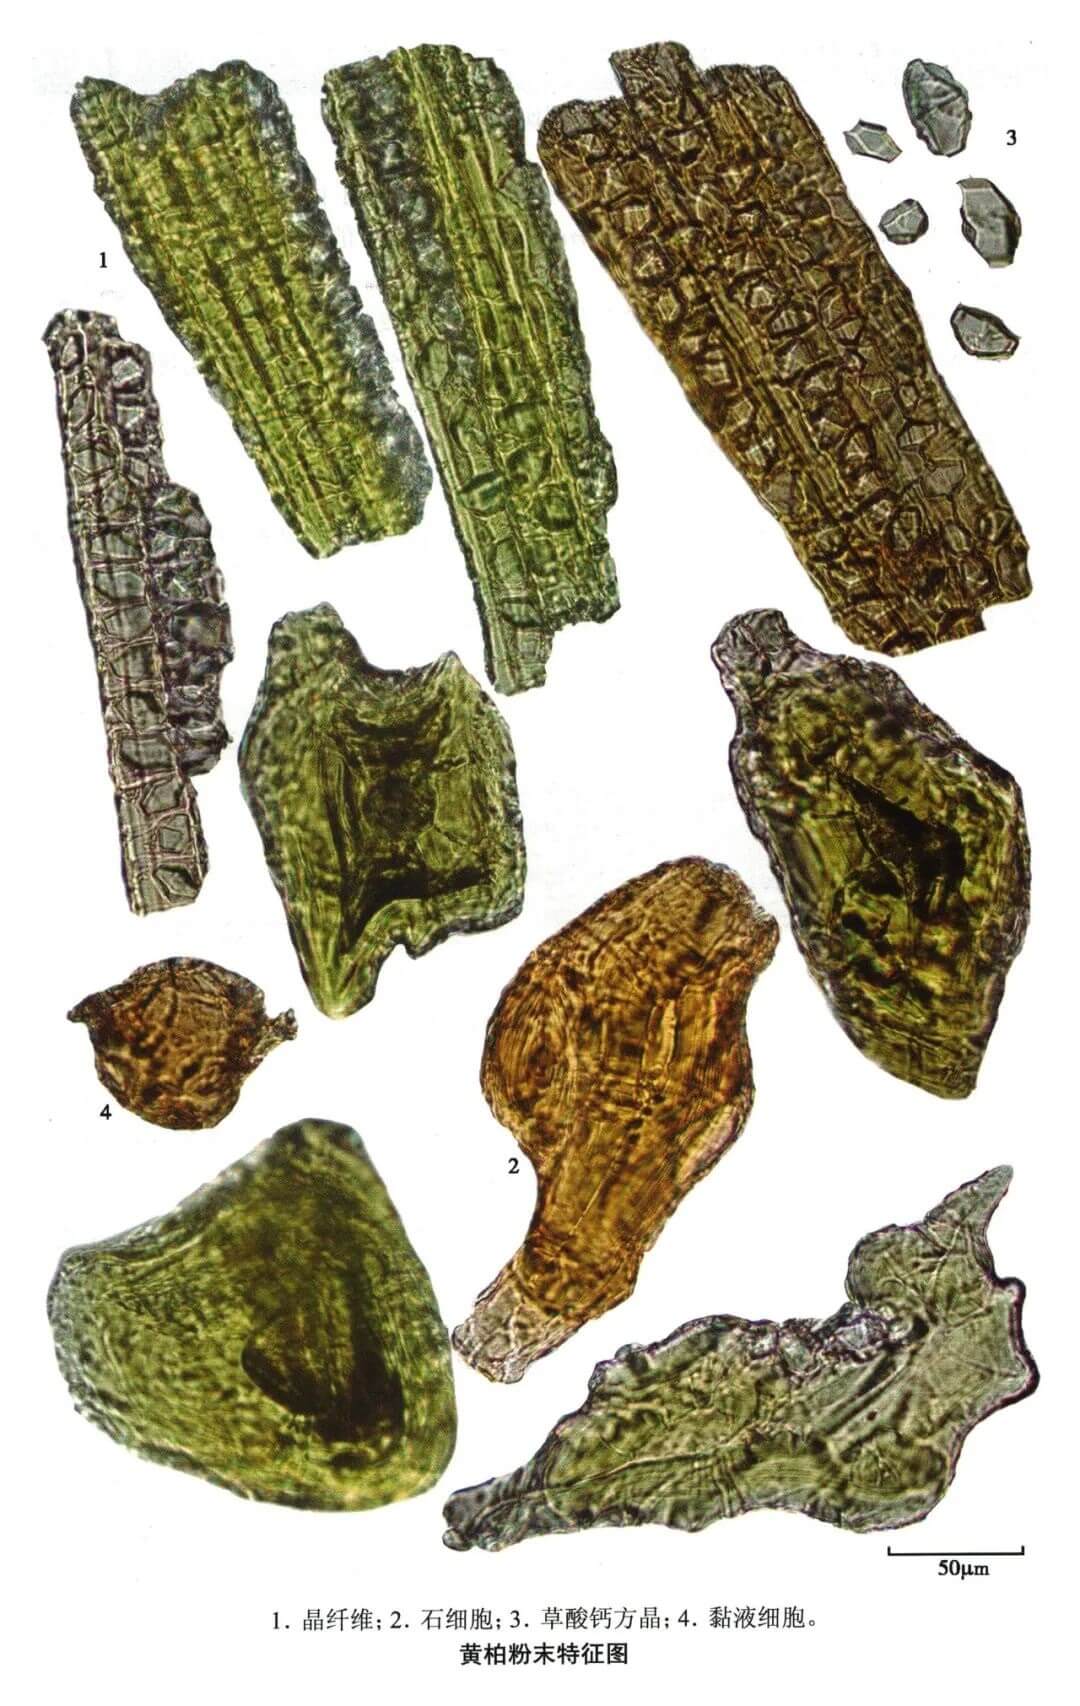

黄柏

| 黄柏 |

|---|

| 【参考标准】 《中国药典》2020年版一部 |

| 【显微鉴别】 本品粉末鲜黄色。纤维鲜黄色,直径16~38μm,常成束,周围细胞含草酸钙方晶,形成晶纤维;含晶细胞壁木化增厚。石细胞鲜黄色,类圆形或纺锤形,直径35~128μm,有的呈分枝状,枝端锐尖,壁厚,层纹明显;有的可见大型纤维状的石细胞,长可达900μm。草酸钙方晶众多。 |

| 【显微重点】 鲜黄色纤维、晶纤维、石细胞。粘液细胞需要用水合氯醛不加热才容易找到。 |

| 【图谱来源】 《中药成方制剂显微图典》 |